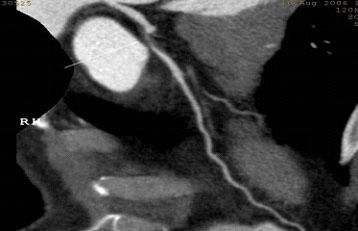

一,德國西門子SOMATOM Definition AS+ 64排128層4D螺旋CT是目前世界上最高端的螺旋CT之一,功能強大,配置齊全,能實現128層0.6mm薄層采集,掃描速度快、範圍大,0.3秒旋轉一周,可産生128層圖像,覆蓋4cm範圍。其主要功能和特點表現在:1、冠脈成像。心髒冠脈掃描僅需要5~8秒,大幅度減少了患者的屏氣時間,冠脈血管成像成功率高,圖像質量優異;2、快速大範圍和高分辨掃描,使全胸腹軟組織、全身和四肢血管、骨關節四維成像更逼真、精确,具有四維智能在線劑量調節,大大減少了射線劑量,對全身掃描可節省66%的射線劑量,極大地減少了射線對人體的危害! 3、器官灌注成像;4、肺功能分析;5、齒科全景成像;6、仿真内窺鏡;7、骨密度測量,等。

64排螺旋CT冠狀動脈血管成像:

1、簡單:無需經動脈插管,隻需象平時靜脈輸液一樣在肘靜脈内推注相對适量對比劑,然後行快速掃描即可完成整個檢查。

2、安全:64排螺旋CT冠狀動脈造影,對比劑用量較少,無需動脈插入導管,患者無需承擔麻醉及動脈插管等帶來并發症的危險。在冠狀動脈血管疾病的篩查、早期診斷、冠狀動脈成形術和搭橋術前、術後血管評價,冠狀動脈起源異常及心肌橋等方面極具優勢。